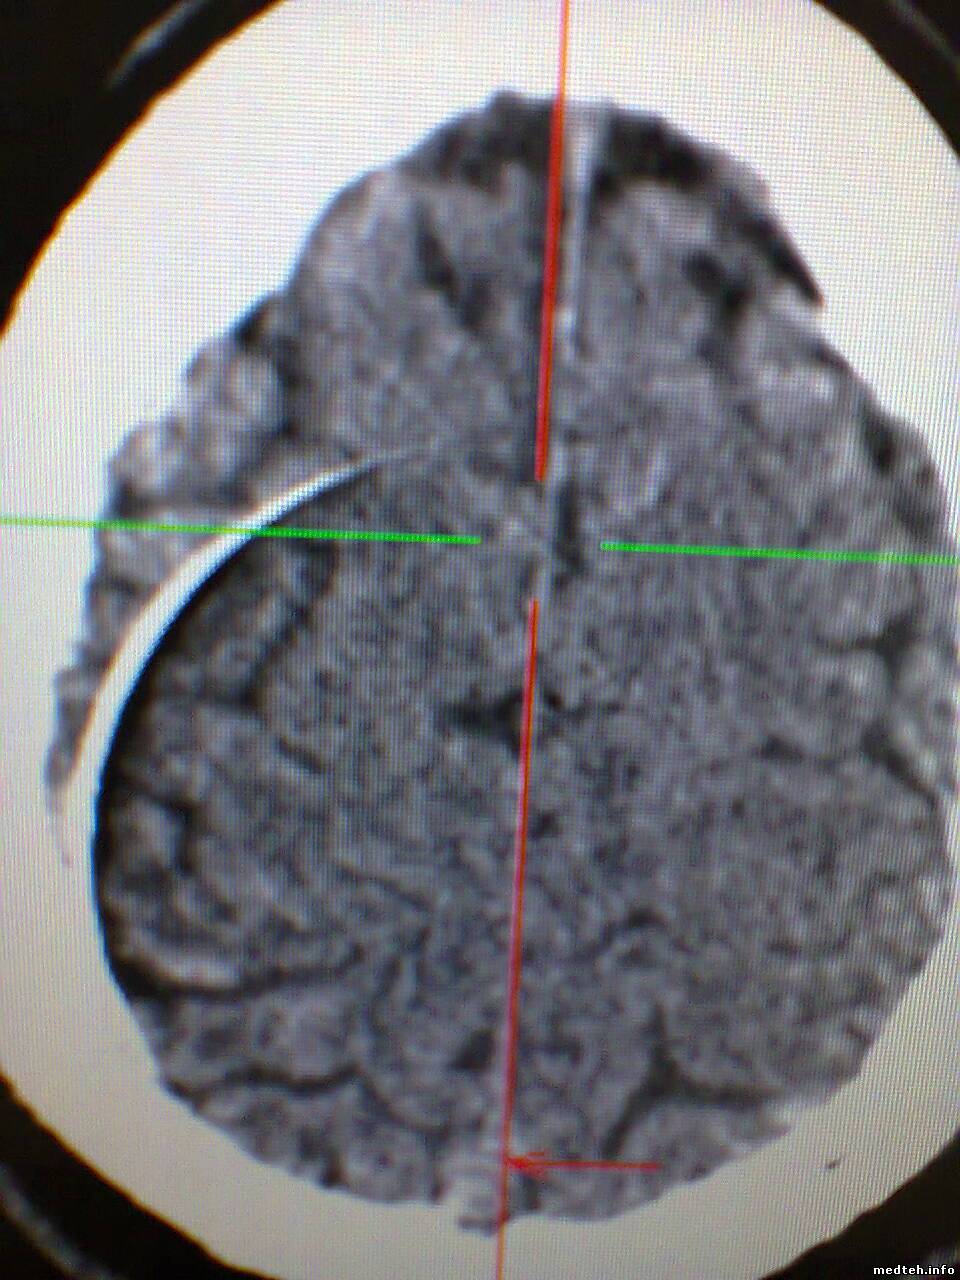

Здравствуйте, появился спиральный артефакт на изображениях, который исчезает примерно на день если провести калибровку по воздуху, думал что дело в модуле датчиков но тест defective channels не показывает ошибок. Что-нибудь кроме датчиков может давать такое изображение? Есть вероятность что детектор как-бы отпаивается? Можно ли тогда запаять его обратно?

1233008.jpg (169.7 Kb) · 7047881.jpg (198.7 Kb) · 0284259.jpg (186.5 Kb) · 0243983.jpg (196.8 Kb) · 3573226.jpg (195.6 Kb)